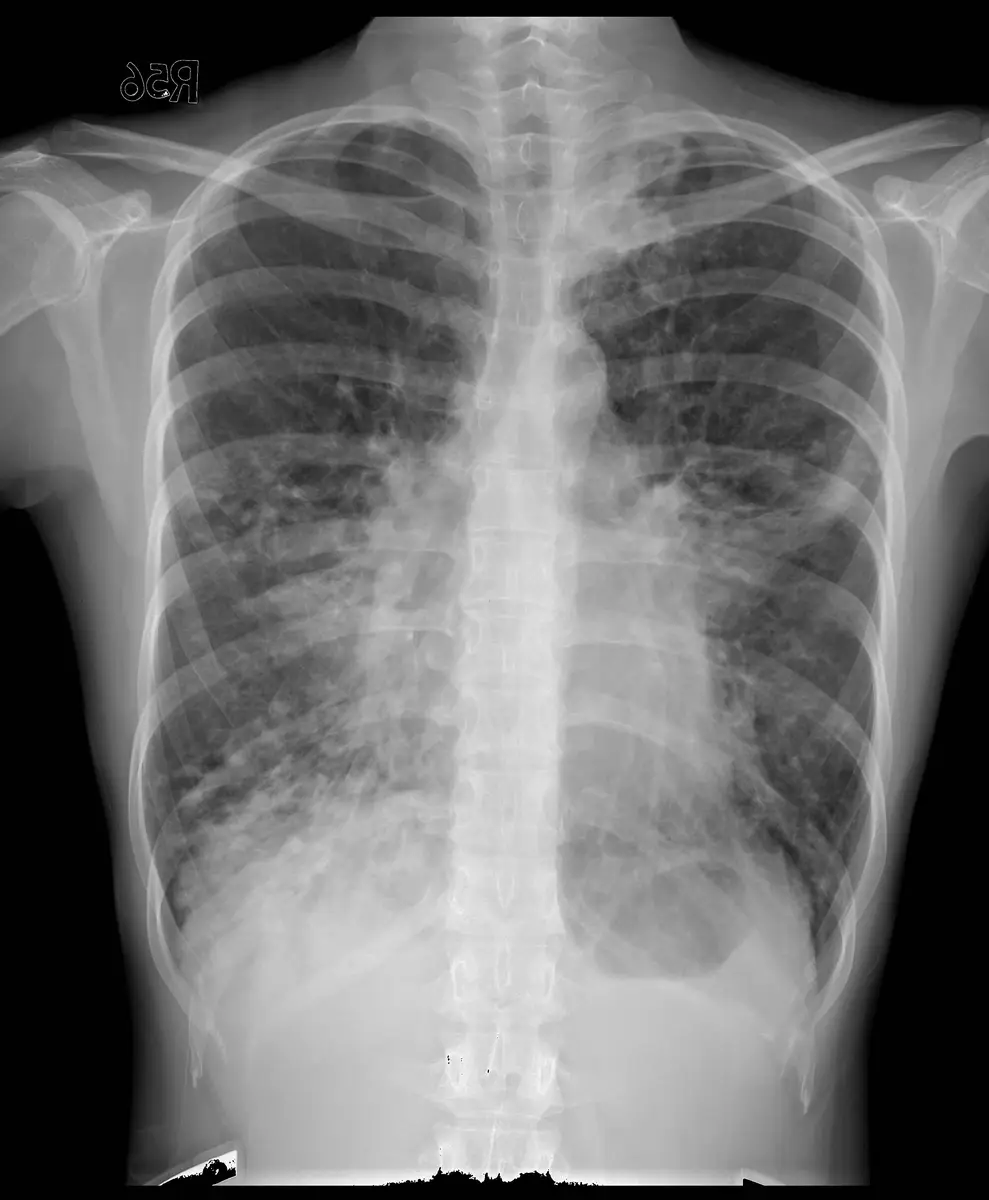

邱女士,因有大量濃痰和咳血至門診就醫,胸部 X光如圖所示,最正確的診斷為:

支氣管擴張症(bronchiectasis)是一種以支氣管永久性異常擴張為特徵的慢性肺部疾病,臨床典型表現為慢性咳嗽、大量膿痰,以及反覆咳血。胸部 X 光可見特徵性的電車軌道徵象(tram-track sign)與環狀陰影(ring shadows),是本題診斷的關鍵。

本題胸部 X 光(後前位,posteroanterior view)顯示:

- 雙側肺野:可見瀰漫性增加的支氣管血管紋理(bronchovascular markings),以中下肺野最為明顯

- 環狀陰影(ring shadows):雙側肺野可見多個小環狀透亮影,代表支氣管橫切面的管壁增厚與管腔擴張,為支氣管擴張症的典型表現

- 電車軌道徵象(tram-track sign):沿支氣管走向可見平行的線狀緻密影,反映支氣管壁增厚且管腔失去正常收窄的特性

- 肺紋理紊亂:整體肺紋理較正常粗亂,伴有局部密度不均勻增加,可能反映黏液栓塞或反覆感染後的纖維化改變

- 心臟及縱膈:大小及位置基本正常,無明顯移位

- 未見:局部實變(consolidation)、氣胸、大量肋膜積液,排除急性大葉性肺炎或肺栓塞的典型影像

上述影像特徵結合病人「大量濃痰與咳血」的臨床表現,高度符合支氣管擴張症的診斷。